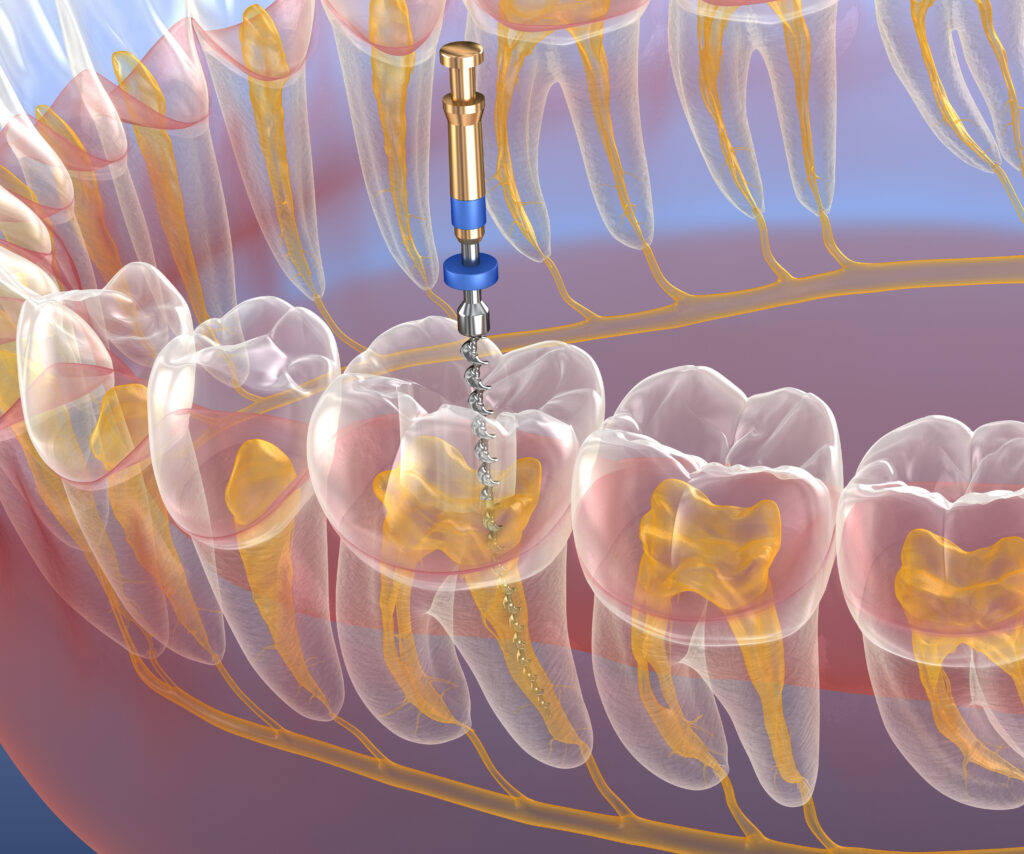

During a root canal, the dentist gently removes the infected pulp tissue and thoroughly disinfects the inner canals of the tooth. Once cleaned, the space is filled with a biocompatible material and sealed to prevent reinfection. In most cases, the treated tooth is then restored with a dental crown to reinforce its structure and appearance — allowing you to chew, speak, and smile with confidence.

Modern endodontic procedures are far more comfortable than their outdated reputation suggests. With advanced anesthesia, rotary instruments, and laser-assisted cleaning techniques, the process is often painless and completed in one or two visits.